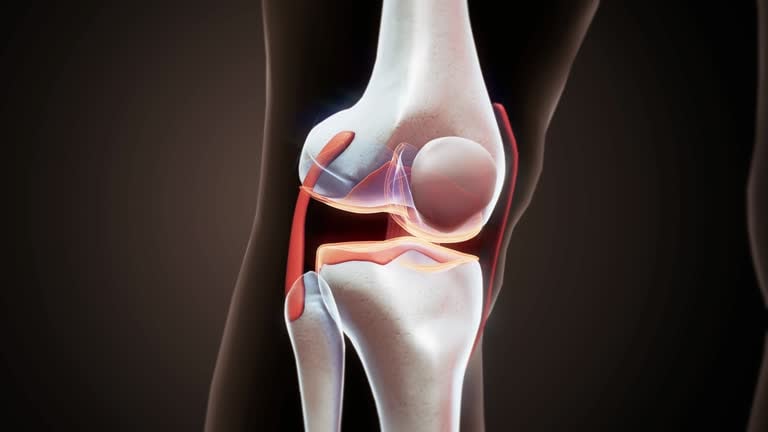

Total knee replacement, also known as total knee arthroplasty, is a surgical procedure designed to relieve pain and restore function in severely diseased knee joints. This procedure is typically recommended for patients suffering from severe arthritis or significant knee injuries that have not responded to conservative treatments such as medications, physical therapy, or less invasive surgeries. The knee joint, which is the largest joint in the body, is composed of the lower end of the thighbone (femur), the upper end of the shinbone (tibia), and the kneecap (patella). In a healthy knee, these bones are cushioned by cartilage, which allows for smooth and pain-free movement. However, in cases of severe arthritis, this cartilage wears away, leading to bone-on-bone contact, pain, and reduced mobility.